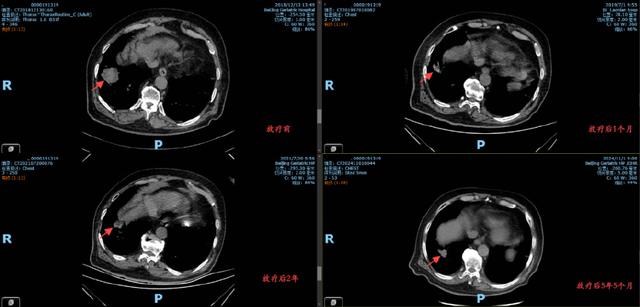

放疗后的复查显示,李大爷右肺下叶的病灶明显缩小,血氧水平得到改善,身体状况显著提升。更令人欣慰的是,自2019年以来,李大爷的病灶未再出现进展,五年随访中始终保持稳定。

从2019年4月至5月,李大爷接受了共30次精准放疗。治疗过程顺利,期间无明显不良反应。放疗团队通过实时影像引导技术,确保每次治疗都精准靶向病灶区域,力求既达到局部控制效果,又避免损伤周围正常组织。